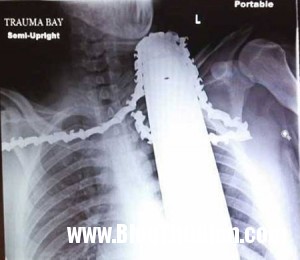

Hình chụp X-quang lưỡi cưa găm chặt vào cổ James.

James được đưa vào Bệnh viện Allegheny thuộc thành phố Pittsburgh để cấp cứu. Tại đây, bác sĩ Christine Toevs cho biết, lưỡi cưa đã may mắn không cứa vào động mạch mà chỉ chạm vào cơ của anh. Nếu ngay từ đầu đã rút lưỡi cưa ra, James sẽ bị mất máu rất nhiều và có thể gặp nguy hiểm tới tính mạng.